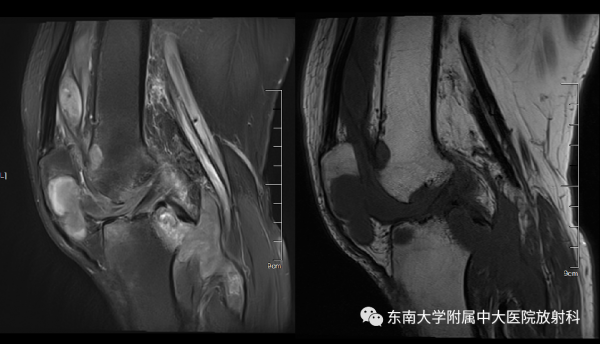

膝关节结核

男,56岁

主诉:左膝活动时疼痛4年,加重1年

患者4年前无明显诱因出现左膝关节疼痛,活动时加重,呈持续性,1年前无明显诱因下感左膝关节疼痛明显。无畏寒发热。查体示:左膝内翻畸形,左膝内外侧压痛,浮髌试验阴性。

影像学表现

作者:冷岩/王敏

来源:东南大学附属中大医院放射科 公众号